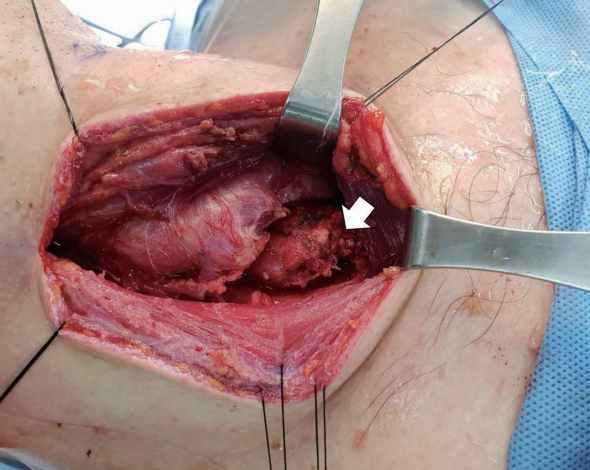

전신마취하에서 수술은 쇄골에서 손가락 두 마디 위에 피부 횡절개를 시행하여 접근하였다. 후인두의 상부에서는 색깔이 투명하고 노란색의 장액성 액체가 나왔으며 탁한 농성분비물의 소견은 없었다. 컴퓨터단층촬영에서 보였던 농양강으로 추정되는 연조직이 갑상선 우엽의 바로 아래에서 기관 뒤를 감싸며 위치했다. 주위 조직들과 염증으로 인한 유착 소견이 있었지만 갑상선의 아래 경과와는 비교적 잘 분리되어 갑상선 기원의 종물을 배제할 수 있었다. 농양강은 일반적으로 피막이 없기 때문에 표면이 비교적 부드러우며 그 경계를 조작하면 잘 터지게 되는데, 갑상선과 분리할 때 이러한 소견들이 없이 비교적 부드럽고, 2 cm 크기로 타원형의 붉은색을 띠는 피막을 가진 고형 종물 소견이 관찰되었다(Fig. 2).

기관 부위와 종물은 유착이 심해서 분리를 할 수 없었다. 종물과 농양강의 감별을 위해 피막을 절개하고 종물의 내부를 관찰하였다. 농양 소견은 없었고, 소량의 염증성 삼출물이 있었고 종물의 대부분이 노란색의 연조직으로 가득 차 있었다. 종물 내부에서 조직 검사를 시행하였다. 기관의 후측면은 반회후두신경의 주행 경로이고, 기관과 분리가 안 되는 큰 종물이 위치하고 있어 신경 손상의 가능성이 높다고 판단하였고, 향후 조직 검사 결과를 확인 후 필요 시 종물의 치료를 위한 2차 수술의 필요성을 보호자에게 설명하고 수술을 종료하였다.